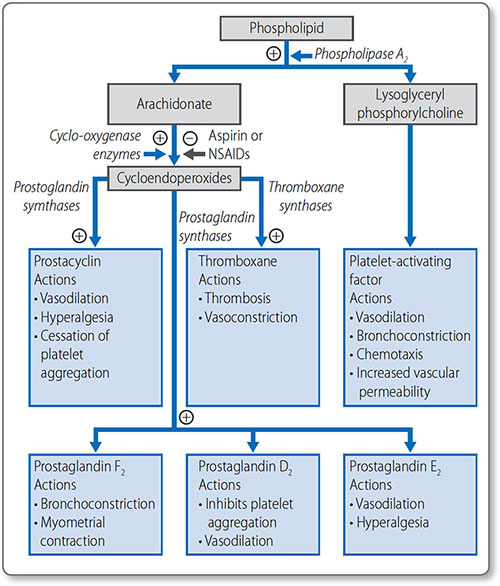

Prostaglandins

Arachidonate is a 20-carbon polyunsaturated fatty acid derived from linoleate. It is the starting point for the basis of the prostaglandins: prostacyclins, thromboxanes and 75leukotrienes (Figure 1.44). These locally acting hormones have a short half-life but have vital functions, including:

|

- Stimulating the inflammatory response

- Regulating local blood flow

- Propagating synaptic transmission

- Sleep induction.